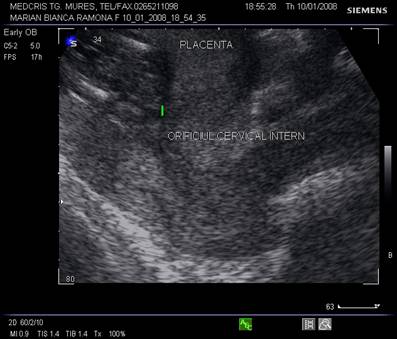

Anomalii de pozitie dupa Hollnder [6]:

I: placenta jos inserata cu marginea sa inferioara intre 0,5 cm si 5 cm de orificiul cervical intern.

II: placenta praevia marginala: marginea sa inferioara la nivelul orificiului cervical intern,

III: placenta praevia partial centrala: o zona a placentei acopera orificiul cervical intern partial.

IV: placenta praevia centrala (completa): intreg orificiul cervical intern este acoperit de masa placentara.

Incidenta placentei praevia variaza cu varsta gestationala. Dupa Wexler [15], in trimestrul II peste 5% din sarcini au ecografic placenta praevia, in timp ce la termen doar 0,5% raman praevia. Acest lucru se datoreaza cresterii placentare si modificarilor suferite de segmentul inferior in timpul sarcinii, ce modifica raportul placentei cu orificiul cervical intern. La multipare incidenta este de 1 la 20, iar la primipare 1 la 1500 sarcini.

Incidenta creste la gravide in varsta, sarcini multiple, dupa chiuretaje uterine si operatii cezariene. Recurenta placentei praevia este de 4-8%, dupa operatie cezariana peste 10%.[9]

Diagnosticul ecografic se face urmarind marginea placentara inferioara si raportul cu orificiul cervical intern. O imagine mai buna necesita vezica urinara in semipletie sau chiar o ecografie transvaginala.

Fig. nr.217. Placenta praevia centrala la 15 saptamani ( linia indica raportul placenta praevia cu orificiul cervical intern)

Fig. nr.218. Placenta praevia complet centrala , la aceeasi sarcina ca in figura precedenta, dar la 28 saptamani gestationale